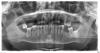

kroha Опубликовано 13 января, 2010 Автор Поделиться Опубликовано 13 января, 2010 спасибо, добавил снимокречь идет о верхней челюстикрайний вверху со стороны L уже удален Ссылка на комментарий

Андрей Опубликовано 13 января, 2010 Поделиться Опубликовано 13 января, 2010 спасибо, добавил снимокречь идет о верхней челюстикрайний вверху со стороны L уже удаленНа верхней челюсте я бы удалил восьмой зуб справа, а возможно и шестой слева. Оставшиеся зубы нужно восстанавить коронками или винирами, смотря в каком они состоянии и как расположены, по снимку этого не видно. Недостающие зубы возмещаются при помощи пяти-шести имплантатов.Можно имплантаты не ставить, а погрыть передние зубы уоронками возместив при их помощи дефект центрального резца, а жевательные зубы сделать съемными. Вообще у Вас есть масса вариантов протезирования. Ссылка на комментарий